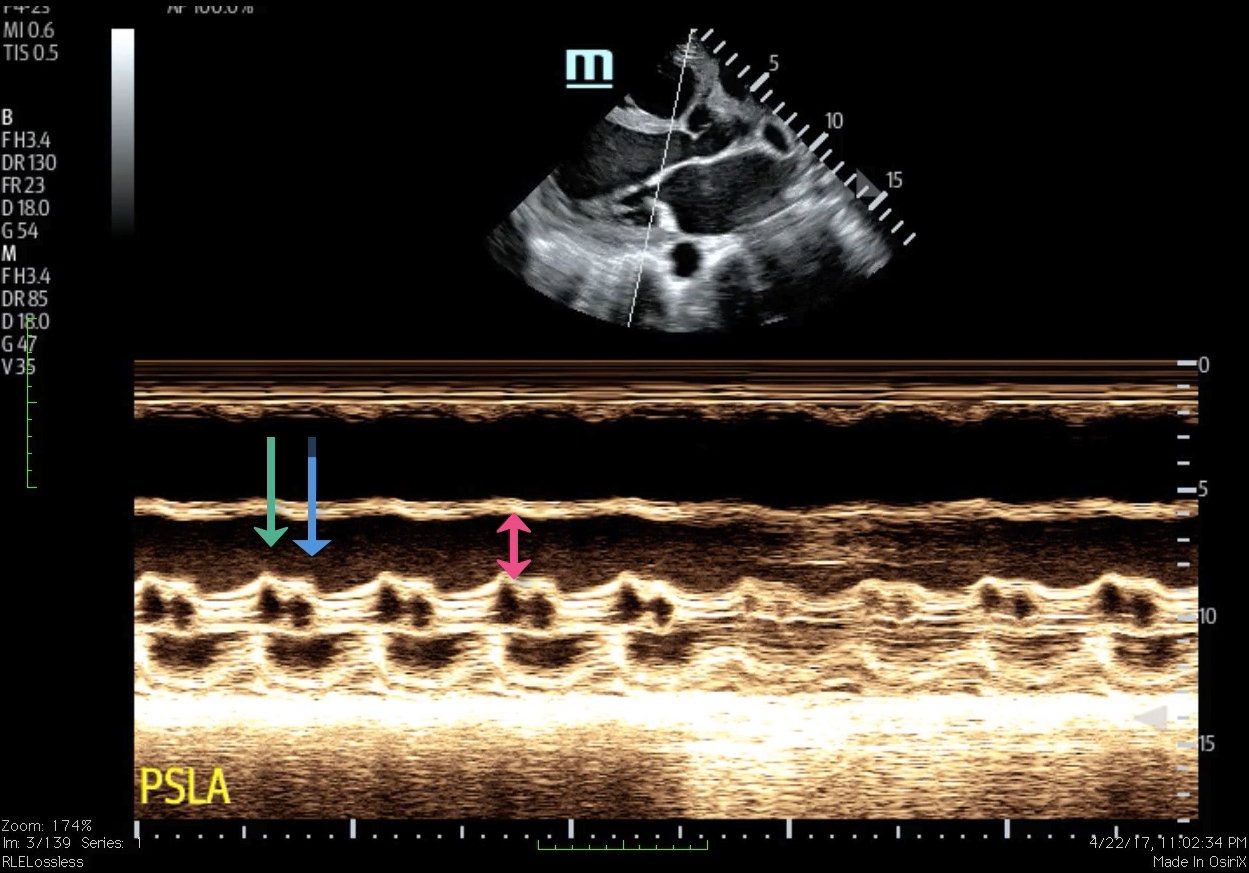

Bedside ultrasound with the phased array probe was used to obtain a parasternal long axis view which demonstrated poor contractility and a severely decreased ejection fraction (EF). M-mode was placed over the anterior leaflet of the mitral valve to create a tracing depicting both the E-wave of early diastole (green arrow) and the A-wave from the atrial kick (blue arrow). The shortest distance between the septum and the mitral valve on the M-mode tracing gives the patient’s E-Point Septal Separation (EPSS) (pink arrow). EF can be estimated using the formula EF=75.5-2.5 x EPSS (in mm). This patient’s EPSS was measured to be 20mm which estimates that she had an EF of 25.5%.

Rapid assessment of EF in the emergency department is critical because patients with heart failure with preserved EF (HFpEF) clinically appear similar to patients with heart failure with reduced ejection fraction (HFrEF). Clinical trials have demonstrated that while therapies such as beta blockers, angiotensin converting enzyme (ACE) inhibitors, and angiotensin receptor blockers (ARBs) are effective in HFrEF, these therapies do not decrease morbidity or mortality in HFpEF, suggesting that there are fundamental differences in their underlying pathophysiology. EF can be estimated using the patient’s E-point septal separation (EPSS) measured on bedside ultrasound.1 EPSS quantifies the separation between the mitral valve leaflet and the septum in early diastole.1 Measurements greater than 7mm predict depressed left ventricular function.2 The sensitivity and specificity of an EPSS measurement of greater than 7 mm for severe systolic dysfunction (left ventricular EF ≤ 30%) were 100.0% (95% confidence interval, 62.9-100.0) and 51.6% (95% confidence interval, 38.6-64.5), respectively.1 Though there is no gold standard for measuring EF,3 the most common modality is the complete echocardiogram which has a sensitivity of 80%, specificity of 88% and positive predictive accuracy of 86%.4 Bedside ultrasound allows physicians to quickly and accurately estimate a patient’s EF using EPSS in order to provide appropriate care in a timely manner.